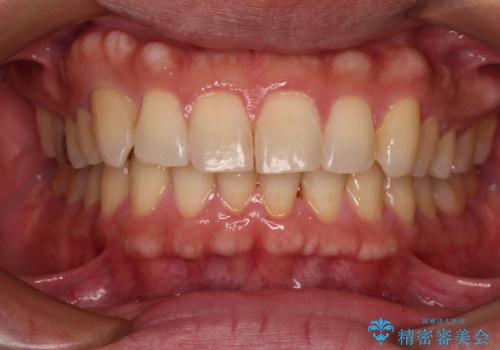

[前歯のねじれ・がたつきを治したい ]ワイヤーとマウスピースの併用矯正治療

![[前歯のねじれ・がたつきを治したい ]ワイヤーとマウスピースの併用矯正治療の症例 治療前](https://seimitsushinbi.jp/wp/wp-content/uploads/2023/11/IMG_0010-1-500x350.jpg?v=1699509973)

![[前歯のねじれ・がたつきを治したい ]ワイヤーとマウスピースの併用矯正治療の症例 治療後](https://seimitsushinbi.jp/wp/wp-content/uploads/2023/11/1c93ab7139a768f1f61b6dd35aac7324-500x350.jpg?v=1699510065)